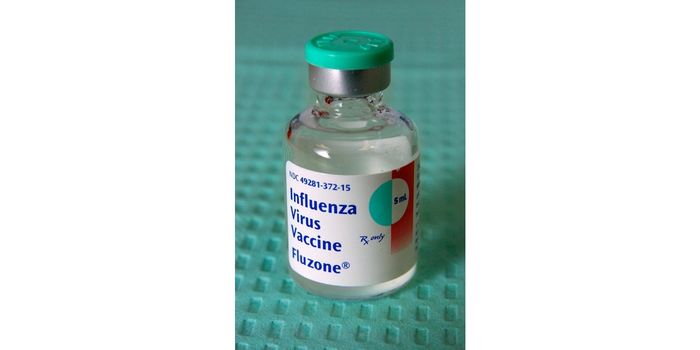

AUG 08, 2023Health & MedicineThe article titled "Evaluation of OVX836: A Promising Universal Influenza Vaccine Candidate" published in ...

OCT 17, 2017ImmunologyThe influenza vaccine may not be as effective as it needs to be for young leukemia patients, who are at an especially hi ...